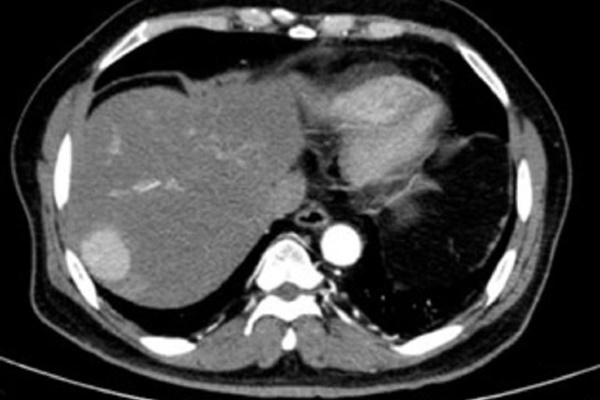

Các nhà nghiên cứu đang thử nghiệm khả năng trì hoãn hoặc ngăn chặn ung thư của sulforaphane. Kết quả đầy hứa hẹn ở cấp độ phân tử đã được nhìn thấy với nhiều loại ung thư, bao gồm khối u ác tính, thực quản, tuyến tiền liệt và tuyến tụy.